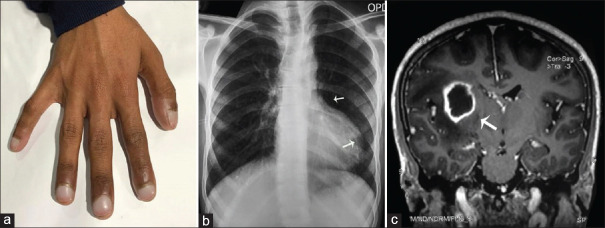

Triad of Clubbing, Boot-shaped Heart, and Brain Abscess in Tetralogy of Fallot.

法洛氏四联症的三联症:跛行、靴状心和脑脓肿。